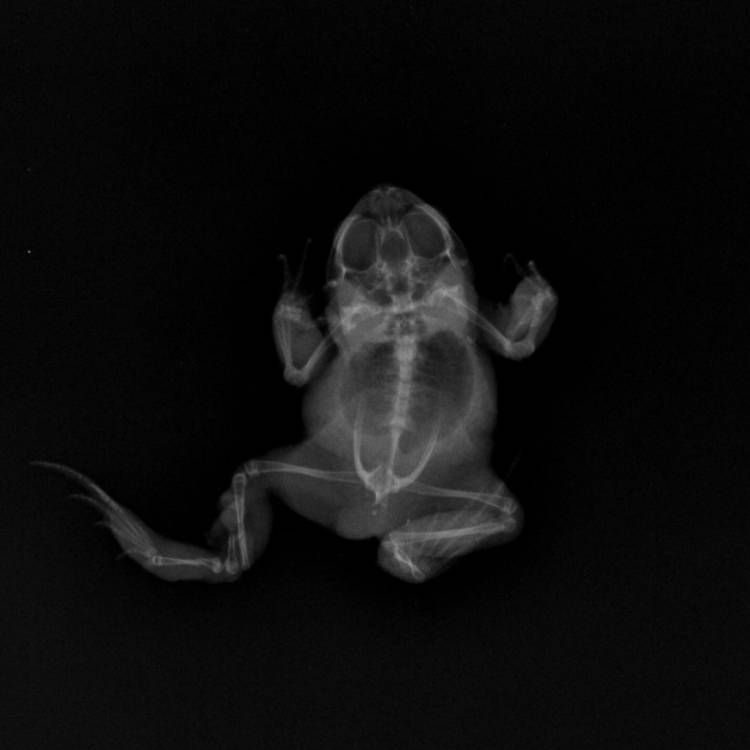

Dr van Huyssteen took X-rays which confirmed that his back left limb was indeed broken and needed to be amputated.

Zap! Little Lego is ready for his X-ray! Credit: Cape Exotic Animal Hospital

Broken in three places, there was, unfortunately, no way Lego's leg could be saved. Credit: Cape Exotic Animal Hospital